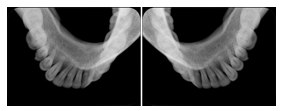

Intra-oral radiography typically involves acquisition of multiple images of various parts of the dentition. Many digital radiographic systems offer customized templates that are used for displaying the images in a study on the screen. These templates may also be referred to as mounts or view sets. The Structured Display Object represents a standard method of encoding and exchanging the layout and intended display of Structured Displays. A structured display object created in this manner could be stored with a study and exchanged with images to allow for complete reproduction of the original exam.

1. A patient visits a General Dentist where a Full Mouth Series Exam with 18 images is acquired. The dentist observes severe bone loss and refers the patient to a Periodontist. The 18 images from the Full Mouth Series along with a Structured Display are copied to a DICOM Interchange CD and sent with the patient to see the specialist. The Periodontist uses the CD to open the exam in his Dental Radiographic Software and consults via phone with the General Dentist. Both are able to observe the same exam showing the images on each user's display using the exact same layout.

Intra-oral Full Mouth Series Structured Display

Figure OO-1. Intra-oral Full Mouth Series Structured Display